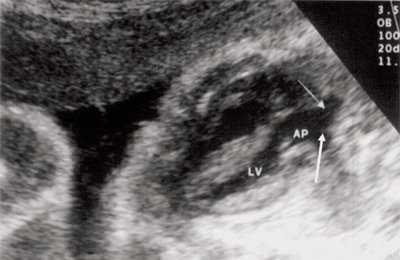

Нагрузка сопротивлением возникает при ситуации, когда выброс крови из желудочков сердца в магистральные сосуды затруднен на уровне полулунных клапанов (стеноз аорты и легочной артерии), подклапанного пространства (идиопатический гипертрофический субаортальный стеноз, подклапанный стеноз аорты или легочной артерии), на протяжении сосудистого русла (коарктация аорты) либо при значительном увеличении выходного сопротивления (синдром Эйзенменгера). В результате затруднения выброса крови резко возрастает напряжение миокарда соответствующего желудочка при относительно стабильном объеме крови, что служит проявлением систолической перегрузки сердца. При систолической перегрузке желудочков сердца независимо от нозологической формы порока полость желудочка, несущего основную нагрузку сопротивлением, умеренно увеличивается в размерах. В ответ на нагрузку сопротивлением на эхокардиограмме выявляется гипертрофия миокарда соответствующего желудочка, и чем больше сопротивление выбросу, тем резче выражена степень гипертрофии миокарда соответствующего желудочка и межжелудочковой перегородки (рис. 1) [3].

Рис. 1. Систолическая перегрузка правого желудочка. Поперечное сечение желудочков сердца при стенозе легочной артерии. Градиент давления правый желудочек - легочная артерия равен 200 мм рт.ст. Выраженная гипертрофия межжелудочковой перегородки и миокарда передней стенки правого желудочка.